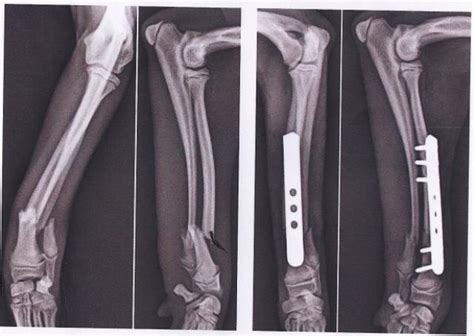

Non ha portato il cane dal veterinario e ha cercato di curare da sola la frattura ad una zampa. Il corpo di una falange è la porzione ossea centrale, compresa tra l'estremità prossimale e l'estremità distale; Le fratture della falange distale sono trattate in base alla sede della frattura e le indicazioni vanno da una riduzione aperta a un semplice splint con immobilizzazione.

La frattura può dipendere da diversi fattori, da traumi più gravi o da usura, soprattutto nei cani anziani. Alcuni dei segni visibili di una gamba rotta non sono molto diversi di quelli negli esseri umani. Ci sono davvero un numero infinito di tipi di fratture ossee che interessano. Le fratture della falange distale sono trattate in base alla sede della frattura e le indicazioni vanno da una riduzione aperta a un semplice splint con immobilizzazione. Falange molti 45 significato del sogno: Cavallo con frattura della terza falange, terapia con cellule staminali del sangue, pieni recupero in meno di 3 mesi, partecipazione al primo concorso post. O quando meno ve lo aspettate e siete preparati a questa eventualità? Curare una frattura nel cane può essere un'operazione abbastanza rischiosa e difficile e proprio per questo è opportuno sempre chiedere consiglio al veterinario oppure optare per una visita specialistica. Migliaia di nuove immagini di alta qualità aggiunte ogni giorno. Scopri i sintomi e la terapia per una corretta guarigione! Frattura composta falange p1 dito indice. Il vostro cane può rompersi una zampa? Laser e lavorazioni a mano questa collana è. Frattura della base della falange prossimale; Segni di frattura nel cane. Buonasera il mio medico curante le ha detto che ormai non ci può fare niente, ma mia moglie si domanda se con il passare del tempo la falange può andare meglio, tanto ormai si e calcificata la frattura. La frattura nel cane è l'interruzione di un segmento osseo, in seguito ad un trauma.